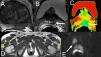

Cáncer de próstata central. Lesión focal hipointensa en la zona central izquierda en el corte axial en T2. La secuencia de RME muestra elevación del pico de la colina (flecha). La secuencia de RMD muestra leve hiperintensidad inespecífica (flecha). El mapa paramétrico CDA en color muestra valores bajos de CDA en el nivel lesional traducido por color azul (flecha), pudiendo cuantificar el valor CDA colocando la región de interés (ROI).

La secuencia dinámica con contraste (RMC) permite la valoración de la vascularización de los tumores y de forma indirecta la angiogénesis25. En la próstata se suele utilizar una adquisición eco de gradiente 3D ponderada en T1 de toda la glándula y vesículas seminales, con una elevada resolución temporal. En nuestro equipo utilizamos la secuencia 3D fast eco de gradiente (tabla 1) (TR/TE: 14/2; ángulo: 12.°; grosor: 4mm; FOV: 26; matriz: 256×160) con una resolución temporal de 4–9s. La secuencia se repite hasta 3–5min de duración total. El análisis de los datos del valor de la intensidad de señal del contraste respecto al tiempo puede obtenerse de tres formas: cualitativo (perfil de la curva), semicuantitativo (cambios en la intensidad de señal) o cuantitativo22. Las medidas cualitativas miden el tipo de perfil de curva: tipo i (captación progresiva), tipo ii (en meseta) o tipo iii (lavado rápido) similar a los estudios de perfusión en la mama. Las medidas semicuantitativas miden y cuantifican la intensidad de señal relativa (la relación entre la mayor intensidad de señal postcontraste y la señal pre-contraste), la pendiente de la curva intensidad/tiempo (que refleja la velocidad del realce) o el área bajo la curva intensidad de señal/tiempo. Estas medidas son simples de obtener en las estaciones de trabajo, pero no son comparables entre distintos equipos (fig. 6). La obtención de parámetros cuantitativos utiliza modelos farmacocinéticos que permiten cuantificar diversos parámetros: ktrans (paso de contraste a través del endotelio desde el compartimento vascular al intersticio), kep (vuelta al espacio vascular) y Ve (fracción del espacio extracelular del tumor)26. Además, con estos datos es posible construir mapas paramétricos que representen la heterogeneidad intratumoral de la distribución vascular. Debemos, sin embargo, considerar la complejidad que existe detrás de estos parámetros, la falta de estandarización y la ausencia de programas de postprocesado de utilización universal. Así, en áreas en donde el tumor tiene una alta permeabilidad vascular (como en la periferia), los valores de ktrans van a depender principalmente del flujo; mientras que en el centro del tumor (en donde el factor limitante es la permeabilidad), dependerán de la superficie de permeabilidad27. La dificultad de interpretación de la secuencia es la falta de estandarización de la misma. De todas formas algunos autores han demostrado que el parámetro más fiable para detectar una neoplasia es la presencia de una pendiente de captación elevada en los primeros segundos acompañada de un lavado rápido14,28.

Cáncer de próstata central y periférico. La secuencia con contraste dinámico, RMC, muestra el mapa paramétrico (flecha) con realce intenso en los primeros segundos traducido con el color amarillo y el lavado rápido traducido con el color rojo en la curva de intensidad/tiempo. Las secuencias funcionales de RME muestran elevación de la colina (flecha blanca) y valor bajo de CDA en el mapa paramétrico de color azul (flecha negra).

La utilización de la secuencia ponderada en T2 de alta resolución es relativamente sensible pero poco específica para localizar el cáncer de próstata33, como se ha descrito en el apartado de técnica (fig. 4) (tabla 2). La combinación de la secuencia ponderada en T2 con una o dos de las secuencias funcionales, como la RME, RMD y RMC (tabla 2) puede mejorar la detección del cáncer de próstata22,34–39. No se ha demostrado cuál podría ser la combinación más eficaz de las secuencias funcionales para complementar la secuencia ponderada en T2, ni tampoco la mayor eficacia si se combinan todas las secuencias funcionales. La integración de la RM de difusión en el protocolo de estudio debería hacerse de forma rutinaria, al haberse demostrado su utilidad combinada con la secuencia ponderada en T239,40 sin que ello represente un aumento del coste de la exploración, como sí sucede con la espectroscopia o la secuencia dinámica con contraste. La integración de la información morfológica y funcional en un único estudio de RM hace prever una mejora en la capacidad diagnóstica de la técnica (fig. 6), especialmente en la zona central transicional28,41. Precisamente, la eficacia diagnóstica mediante RM del cáncer en la glándula central es inferior a la descrita para la glándula periférica. Ello es debido a la presencia de hallazgos similares en la RM morfológica y funcional en la hipertrofia benigna, la prostatitis y el cáncer41,42. Una de las ventajas de la técnica funcional es la de proporcionar información para predecir el grado de diferenciación tumoral, que se correlaciona con las cifras de los marcadores tumorales específicos prostáticos43,44; estudios preliminares parecen objetivar la correlación entre cifras más elevadas de marcadores tumorales con parámetros de imagen funcional más patológicos e indicativos de neoplasias más indiferenciadas. Recientemente se ha demostrado la utilidad de combinar la información integrada en RM con parámetros clínicos como el porcentaje de PSA libre o la densidad de PSA (relación entre el valor del PSA y el tamaño de la próstata) para así seleccionar mejor los pacientes candidatos a ser biopsiados, frente a la indicación actual de biopsiar a todos los pacientes con PSA >4ng/ml37,45. Se trataría de seleccionar a los pacientes con mayor riego clínico de presentar cáncer para realizar una exploración de RM y así intentar biopsiar con mayor precisión a aquellos pacientes en los que haya sospecha de cáncer en la RM funcional. Con estos nuevos algoritmos propuestos se evitarían un número significativo de biopsias innecesarias de pacientes con PSA elevado, debido al elevado valor predictivo negativo de la RM para el cáncer de próstata. Además, la propuesta de realizar la RM prebiopsia evitaría la presencia de los artefactos postbiopsia debidos a hemorragia o fibrosis que pueden interferir en la correcta interpretación del estudio de RM prostática (tabla 2)13,14.